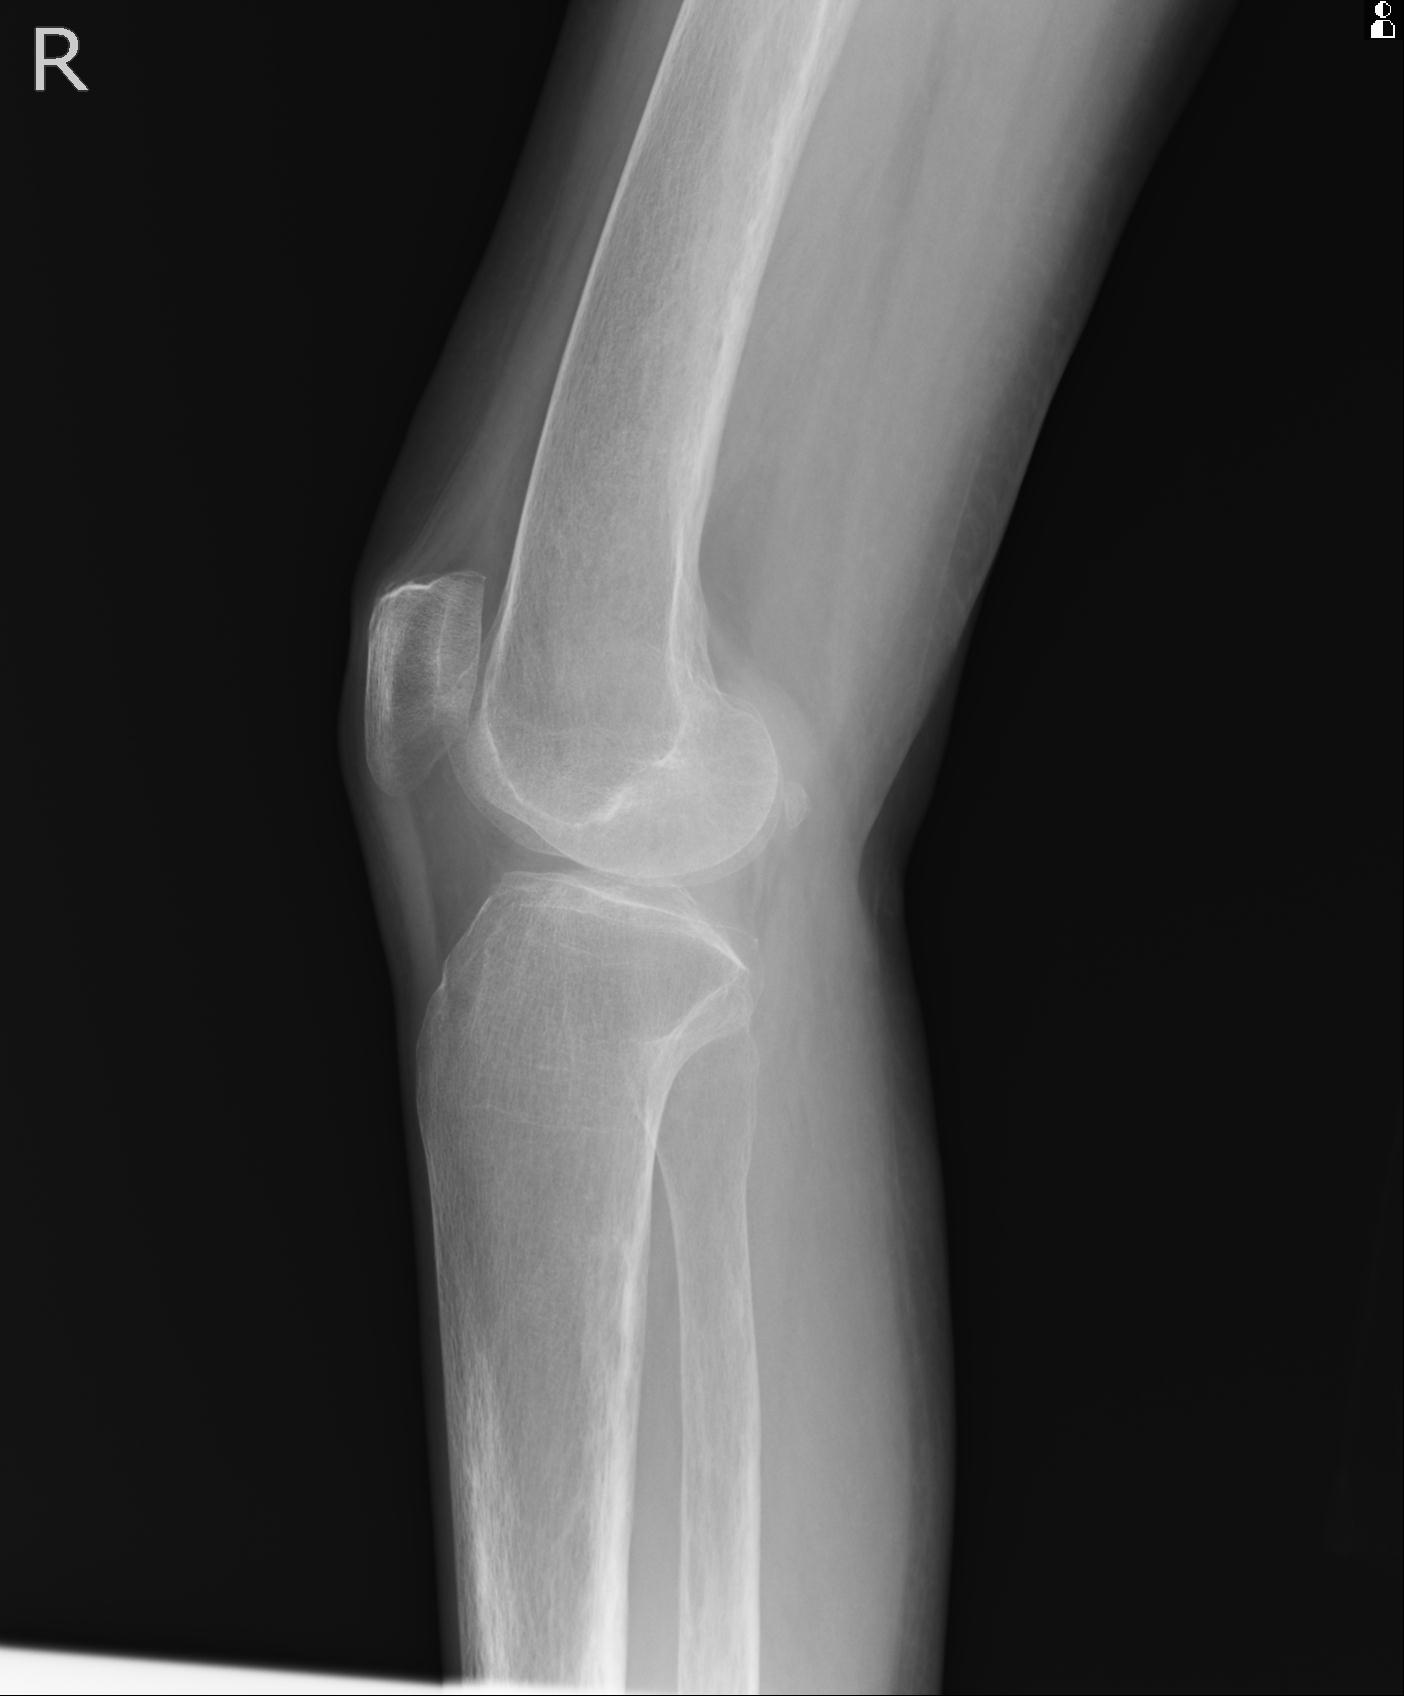

49554 3/13 膝 4R 3/16 4R 1/18 2R 78歳男性 膝蓋骨骨折